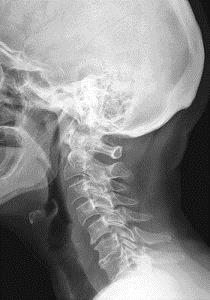

Очень важна диагностическая сторона в унковертебральном артрозе шейного отдела позвоночника. Наш организм подвержен различным заболеваниям, им иногда свойственно иметь схожую симптоматику. Поэтому, очень существенно помимо визуального осмотра и записи в амбулаторной карте о том, что, где и как болит, пройти аппаратное обследование для подтверждения симптомов и постановки точного диагноза.

Итак, врач тщательно расспрашивает больного, делает выводы, находит самые болевые точки в зоне шеи, которые являются локализацией патологических мышечных спазмов. Для подтверждения своих выводов доктор направляет вас на рентгеновский снимок, его делают в двух проекциях. Иногда такого снимка бывает недостаточно, врач может направить на МРТ (магнитно-резонансная томография). Специалисту важно для постановки такого диагноза как унковертебральный артроз на снимках увидеть остеофиты (новообразования имеющие схожесть с крючком), также признаки поражения нервной ткани и кровеносных сосудов в зоне шеи. Если такой диагноз подтверждается обследованием, доктор назначает вам индивидуальное лечение.